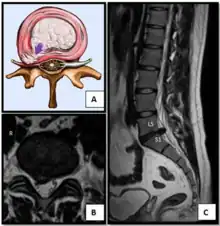

- Magnetic resonance imaging is the gold standard study for confirming a suspected LDH. With a diagnostic accuracy of 97%, it is the most sensitive study to visualize a herniated disc due to its significant ability in soft tissue visualization. MRI also has higher inter-observer reliability than other imaging modalities. It suggests disc herniation when it shows an increased T2-weighted signal at the posterior 10% of the disc. Degenerative disc diseases have shown a correlation with Modic type 1 changes. When evaluating for postoperative lumbar radiculopathies, the recommendation is that the MRI is performed with contrast unless otherwise contraindicated. MRI is more effective than CT in distinguishing inflammatory, malignant, or inflammatory etiologies of LDH. It is indicated relatively early in the course of evaluation (<8 weeks) when the patient presents with relative indications like significant pain, neurological motor deficits, and cauda equina syndrome. Diffusion tensor imaging is a type of MRI sequence used for detecting microstructural changes in the nerve root. It may be beneficial in understanding the changes that occur after herniated lumbar disc compresses a nerve root, and might help in differentiating the patients that need surgical intervention. In patients with a high suspicion of radiculopathy due to lumbar disc herniation, yet the MRI is equivocal or negative, nerve conduction studies are indicated.[46] T2-weighted images allow for clear visualization of protruded disc material in the spinal canal.

MRI scan of large herniation (on the right) of the disc between L4 and L5 vertebrae